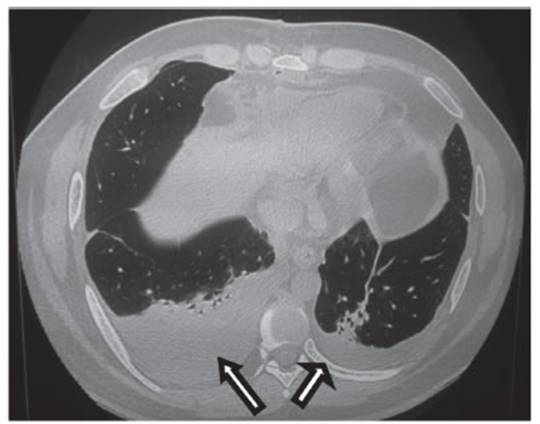

izquierda (flecha Figura 1). A nivel de tórax ensanchamiento de

mediastino anterior con edema difuso de la grasa mediastinal,

líquido tabicado y varias colecciones de aspecto inflamatorio, hacia el

lado derecho colección con aire interno de 2,2 cm y otra en el borde

izquierdo adyacente a la ventana aortopulmonar de

mayor tamaño que mide 5,2 × 3,5 cm de similares características (Figura

2), además, infiltrado parenquimatoso adyacente en bases pulmonares

bilaterales con broncograma aéreo (Figura

3).